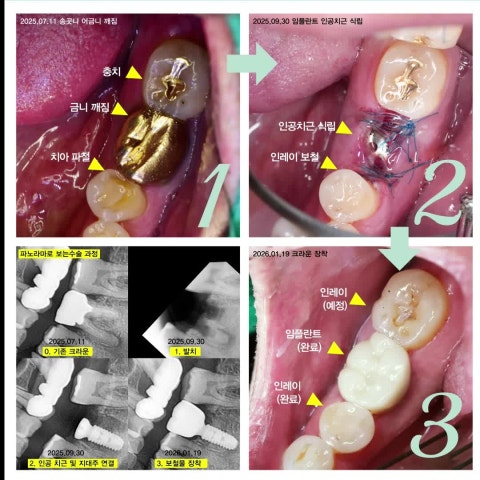

오목교역치과에서 임플란트 수술 과정 알려드립니다. (20250709)

자연치아와 유사하고 지지력도 높아 치아가 완전히 손실된 경우에 가장 적합한 임플란트는 보통...